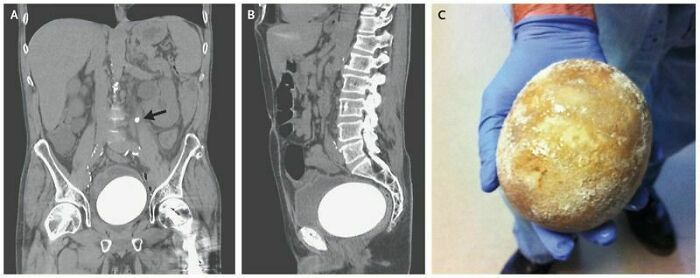

Antes y después de una operación de duplicación craneofacial